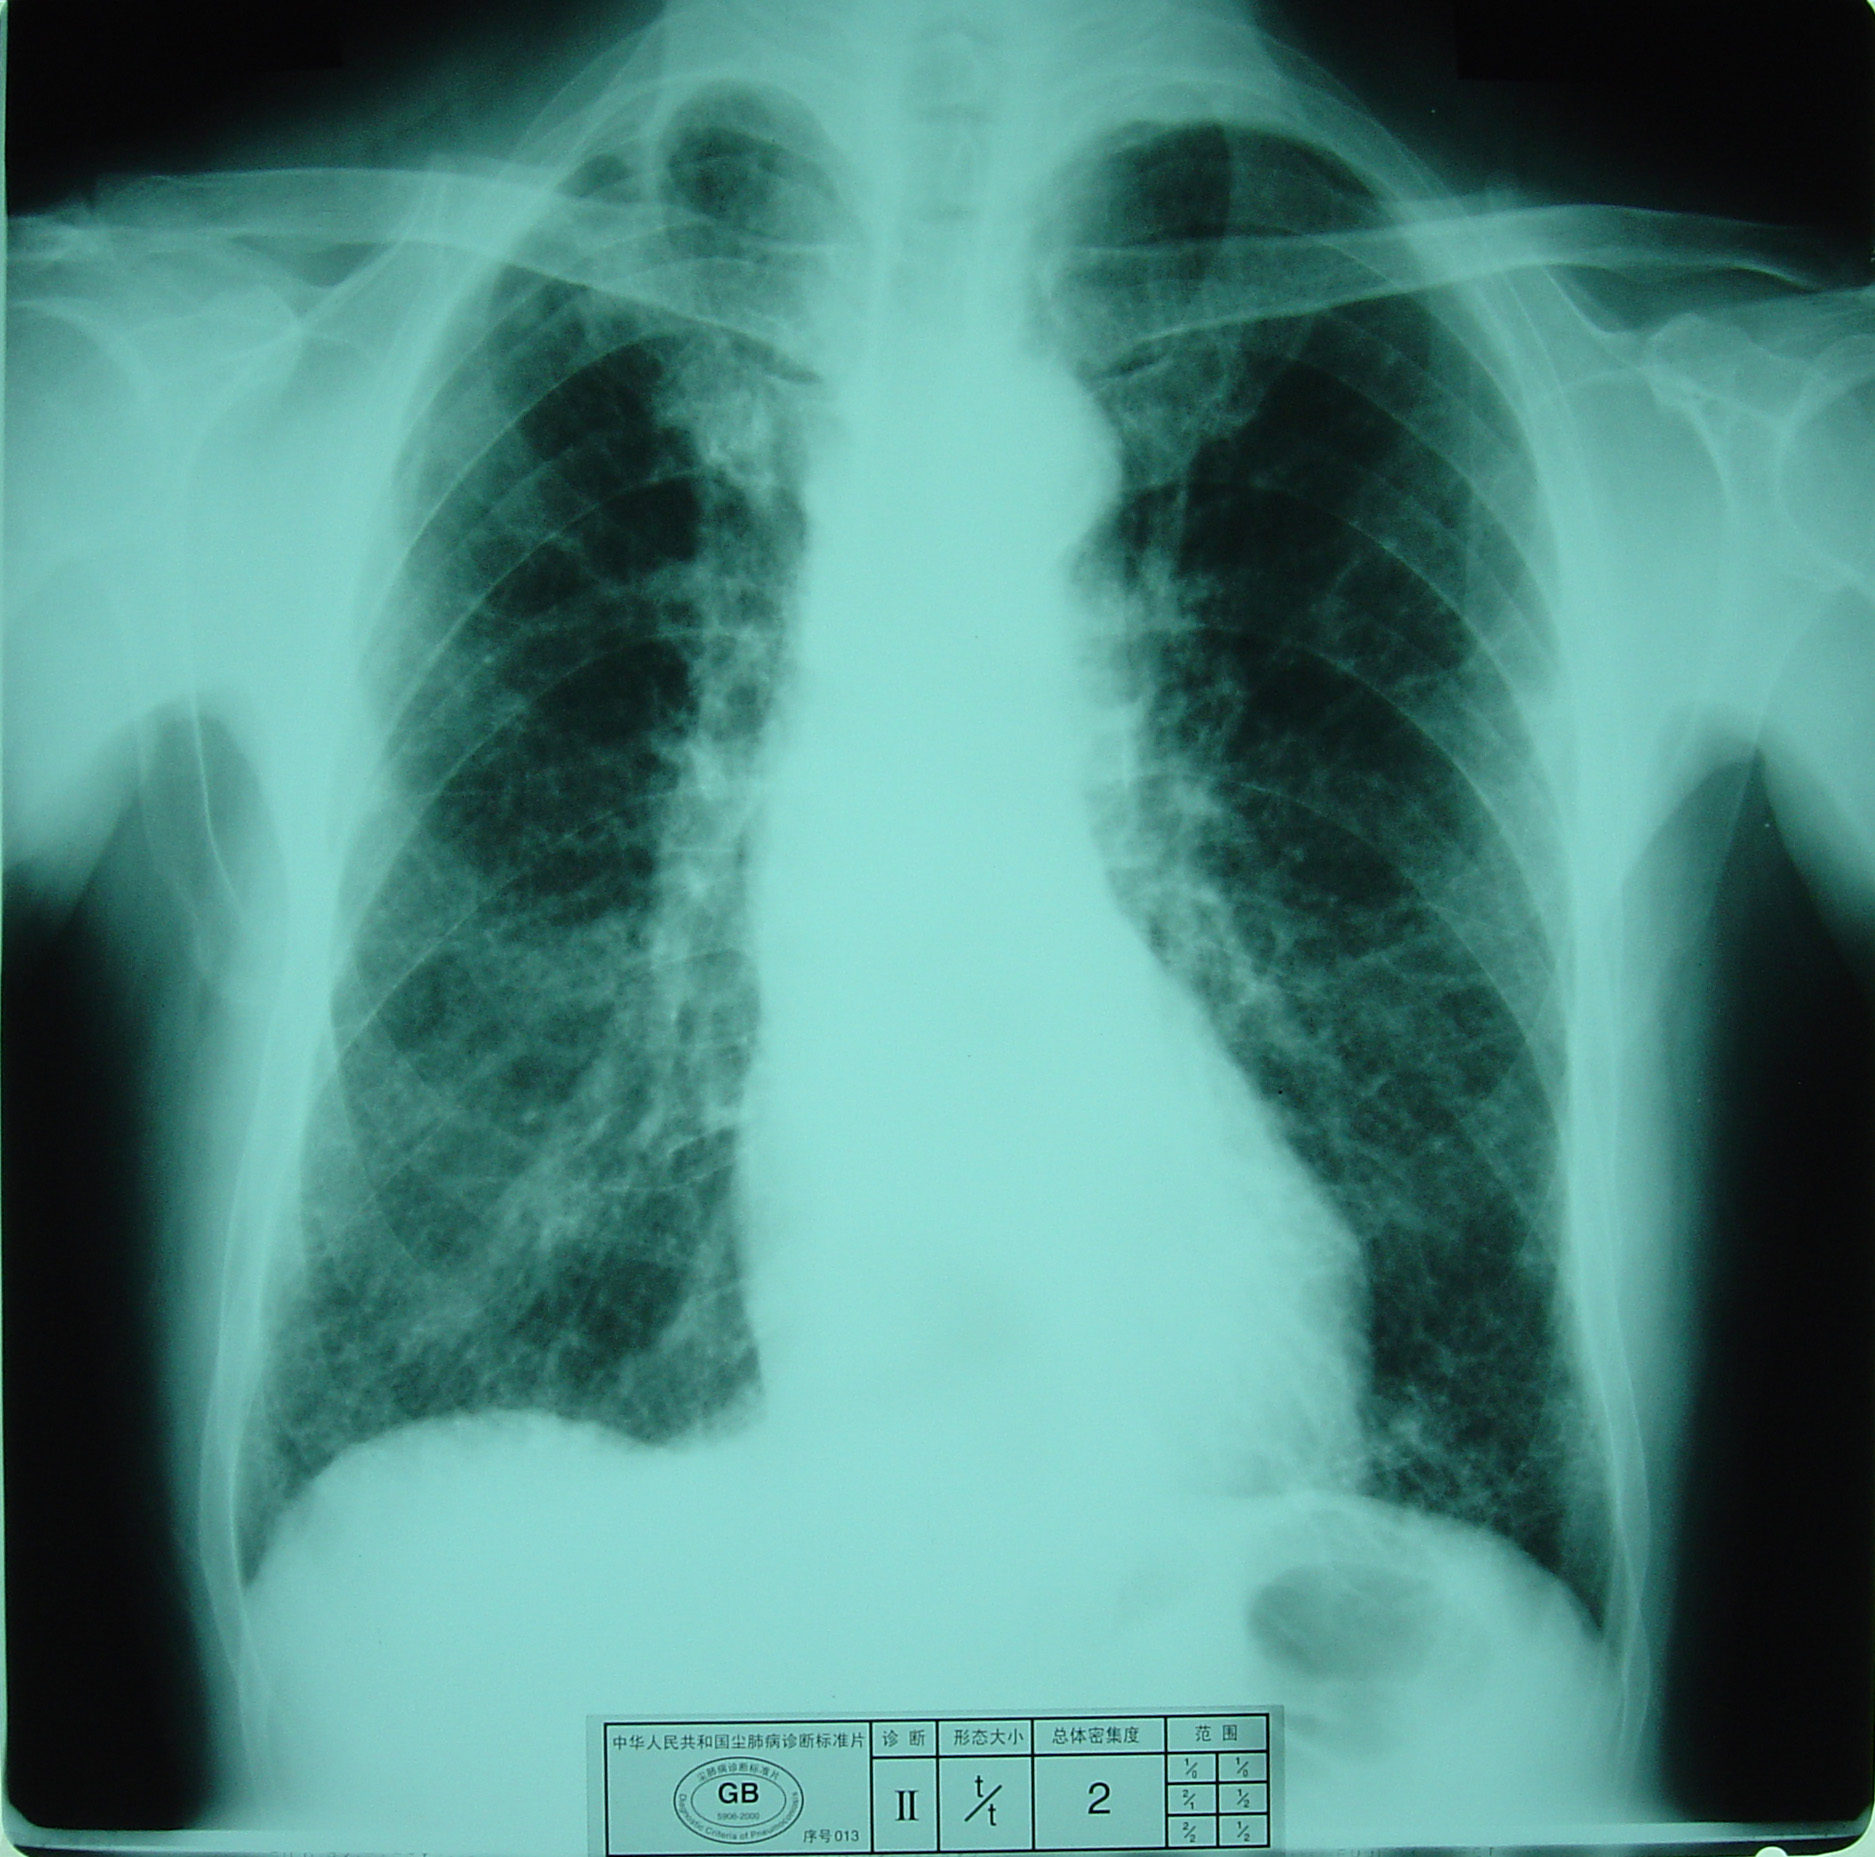

(2)X射线胸片表现:矽肺X射线胸片影像是肺组织矽肺病理形态在X射线胸片的反映,是“形”和“影”的关系,与肺内粉尘蓄积、肺组织纤维化的病变程度有一定相关关系,但由于多种原因的影响,并非完全一致。这种X射线胸片改变表现为X射线通过病变组织和正常组织对X射线吸收率的变化,呈现发“白”的圆形或不规则形小阴影,作为矽肺诊断依据。X射线胸片上其他影像,如肺门变化、肺气肿、肺纹理和胸膜变化,对矽肺诊断也有参考价值。在X射线胸片上,肺野内直径或宽度不超过10mm的阴影。小阴影按其形成分为圆形和不规则形两类。

2)不规则形小阴影:多为接触游离二氧化硅含量较低的粉尘所致,病理基础主要是肺间质纤维化。表现为粗细、长短、形态不一的致密阴影。阴影之间可互不相连,或杂乱无章的交织在一起,呈网状或蜂窝状;致密度多持久不变或缓慢增高。按其宽度可分为s(<1.5mm)、t(1.5~3.0mm)、u(3.0~10mm)三种类型。早期也多见于两肺中下区,弥漫分布,随病情进展而逐渐波及肺上区。

不规则形小阴影(t类小阴影)

a) 有总体密集度2级的小阴影,分布范围超过4个肺区;

b)有总体密集度3级的小阴影,分布范围达到4个肺区。

尘肺贰期

尘肺贰期

尘肺贰期

尘肺贰期

尘肺贰期